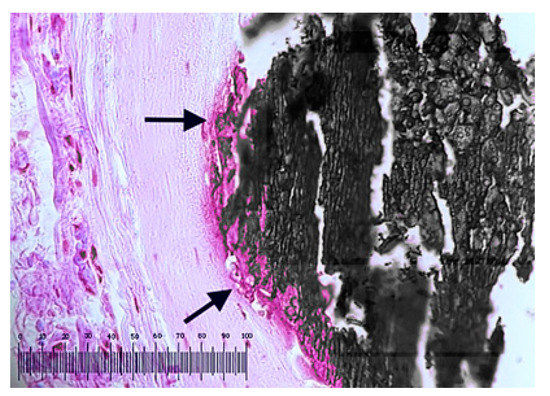

3.3. Evaluation of Tissue/Stents Interface by Histopathological Analysis of Surrounding Tissue